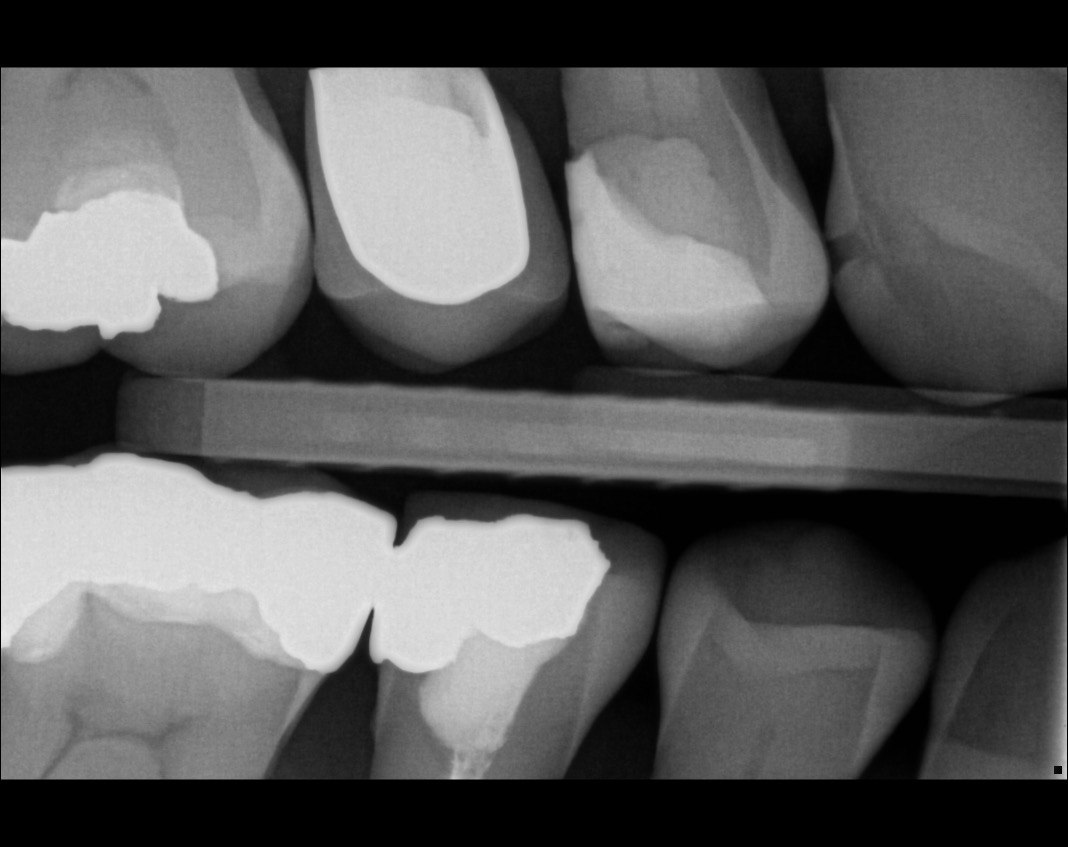

Question 11: Which materials cannot be seen in the print of the X ray?

Question 12: What option cannot be selected for the following X ray?

Question 13: What option cannot be selected for the following X ray?

Question 14: Which surface shows overhang restoration?

Question 15: Which surface shows overhang in the restoration?

Question 16: Which surface shows overhang?

Question 17: Which surface shows overhang?

Question 18: Which surface shows overhang?

Question 19: Which option can be chosen for the tooth # 3.6?

Question 20: which tooth shows defective resotration?

Question 21: What option is can be selected for distal tooth # 4.6?

Question 22: Which surface shows defective restoration?

Question 23: Which surface shows overhang?

Question 24: Which surface shows defective restoration?

Question 25: Which surface shows open margin?